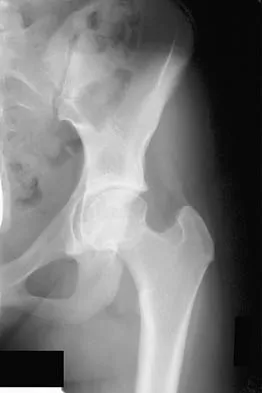

Figures 9a and 9b show the radiographs of a 12-year-old girl who has had right hip pain for the past 4 months. She reports that the pain is so severe that she is unable to walk and is now using a wheelchair. Examination reveals pain with any attempted range of motion. Management should include

Explanation

In addition to mild hip dysplasia, the radiograph shows an osteoblastic lesion of the right ilium. The patient's symptoms are much more severe than is typical for late hip dysplasia. MRI can determine the extent of the lesion in the bone and soft tissues. Following work-up and biopsy, the patient was diagnosed with Ewing's sarcoma. Springfield DS, Gebhardt MC: Bone and soft tissue tumors, in Morrissy RT, Weinstein SL (eds): Lovell and Winter's Pediatric Orthopaedics, ed 5. Philadelphia, PA, Lippincott Williams and Wilkins, 2001, pp 507-518, 542-544.